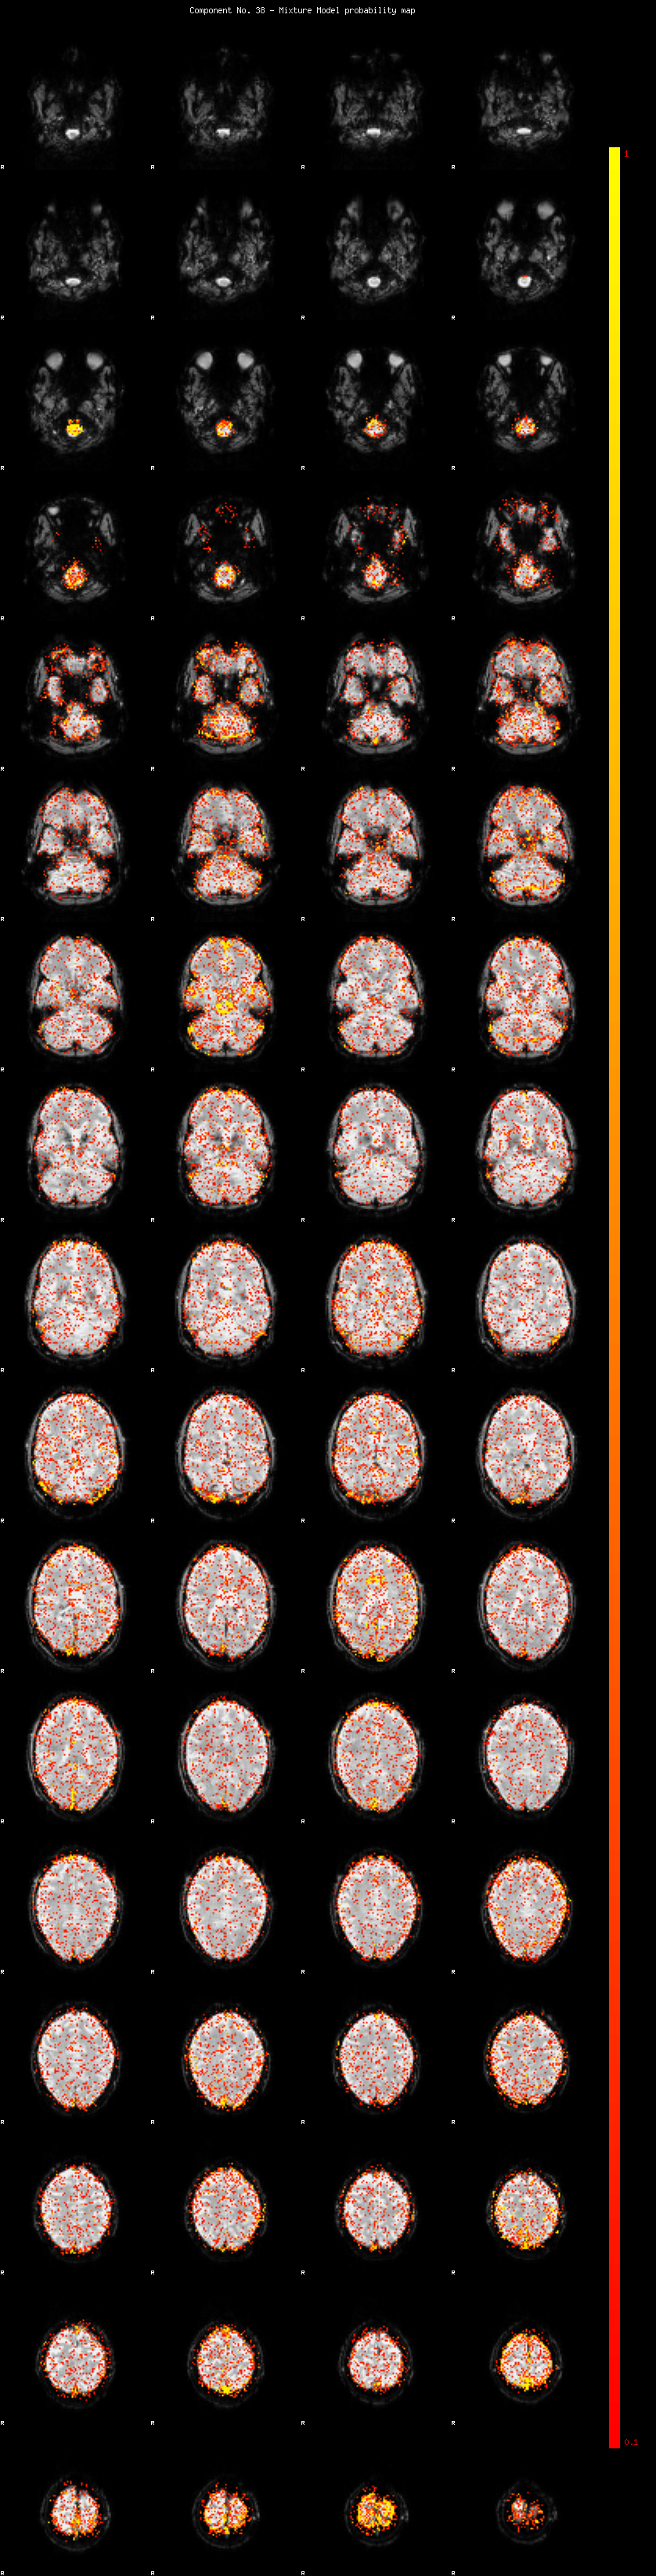

IC_38 Mixture Model fit

Means : 0.000000 2.388733 -2.248957

Vars : 1.000000 1.681692 1.288466

Prop. : 0.920503 0.041495 0.038002